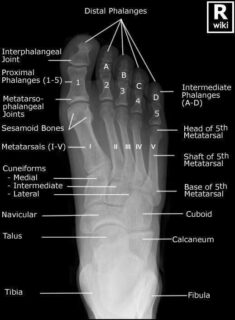

Las radiografías, generalmente llamadas rayos X, producen imágenes como sombras de huesos y ciertos órganos y tejidos. Las radiografías son muy buenas para detectar problemas óseos. Pueden mostrar algunos órganos y tejidos blandos; sin embargo, la MRI y la CT suelen crear mejores imágenes de los mismos. Aun así, las radiografías son rápidas, fáciles de obtener y menos costosas que los otros estudios, por lo que se pueden usar para obtener información rápidamente.

Un tubo especial dentro de la máquina de rayos X emite un haz de radiación controlada. Los tejidos del cuerpo absorben o bloquean la radiación en diferentes grados. Los tejidos densos como los huesos bloquean la mayor parte de la radiación, pero los tejidos blandos, como la grasa o los músculos, bloquean menos radiación. Después de pasar por el cuerpo, el haz alcanza una pieza de un fragmento de película o un detector especial. Los tejidos que bloquean altas cantidades de radiación, como los huesos, aparecen como áreas blancas en un fondo negro. Los tejidos blandos bloquean menos radiación y aparecen en tonos de gris. Los órganos que contienen principalmente aire (como los pulmones) aparecen en negro. Los tumores son por lo general más densos que el tejido que los rodea, por lo que suelen verse en tonos grises más claros.